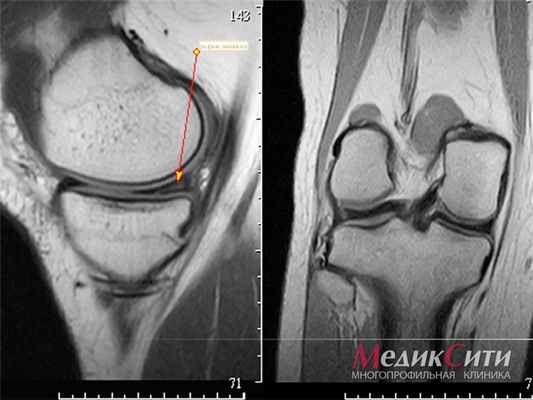

(Слева) Рентгенография в боковой проекции: признаки остеопении, наличия выпота в суставе и мягкотканного образования в заднем отделе без очевидной костной деструкции. Такая картина не является специфичной.

(Справа) МРТ, сагиттальная проекция, режим Т1 с подавлением сигнала от жира: визуализируется образование, представляющее собой скопление жидкости; МРТ в аксиальной проекции подтверждает, что это подколенная киста. Обратите внимание на утолщенную контрастированную стенку кисты, указывающую на наличие синовита, аналогично тому, который визуализируется в суставе. Определяются характерные для РА выраженное истончение хряща, небольшие эрозии и отек костного мозга.